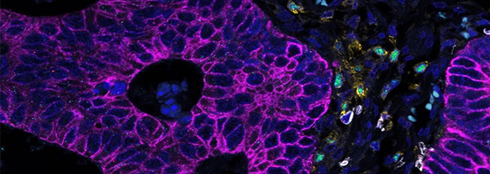

자궁경부암 조직에서 CD163+ / CD68+, IL1B+ / IL10+ 표지자로 종양 관련 M1/M2 대식세포를 매핑하였습니다.